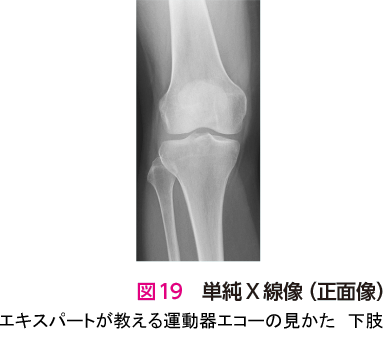

症例 7大腿骨内顆軟骨損傷

前述のように変形性膝関節症においてエコー検査の診断価値は低い.また,私自身も図18のエコー像で初診時に指摘できる自信はない.しかし,エコー検査を用いることで,注射をさまざまなポイントにエコーガイド下に安全かつ正確に打つことができる.そのため,私にとって形性膝関節症の診療におけるエコー検査は変必要不可欠なツールとなっている3).